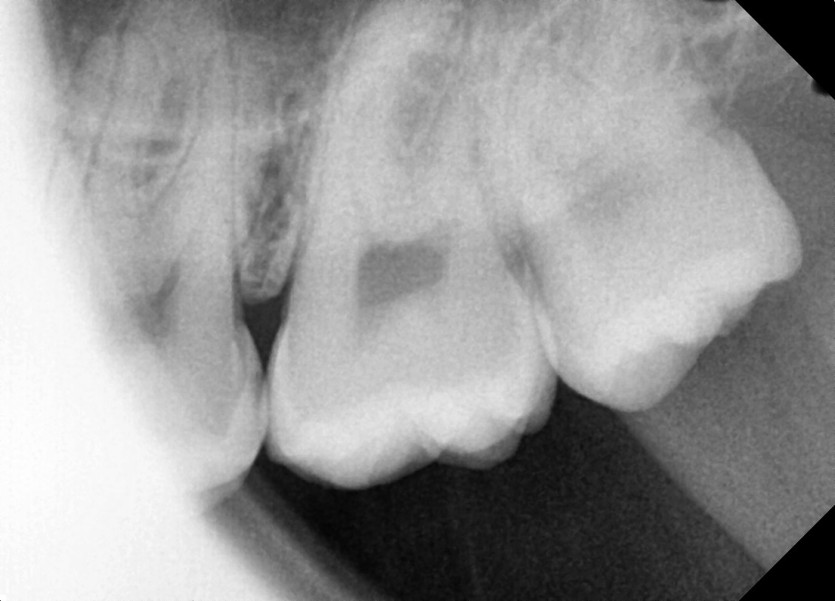

#28,38 사랑니 발치

구강 외과 전문의가 당일 발치하였습니다.